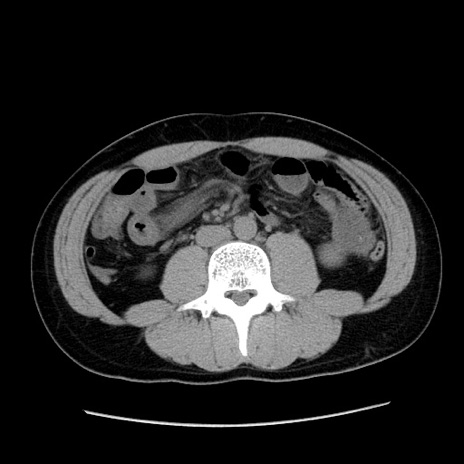

症例36(横断像)

【症例】20歳代 男性

【主訴】心窩部痛

【現病歴】今朝より上腹部痛あり。一旦軽快していたが再度出現したため救急要請。昨日夕に白身の魚を含む刺身を食べた。

【身体所見】BP 136/89mmHg、HR 74/min、BT 37.0℃、腹部:膨満、軟、心窩部に圧痛あり。反跳痛なし、筋性防御なし、腸雑音やや亢進あり。

【データ】WBC 17700、CRP 0.48